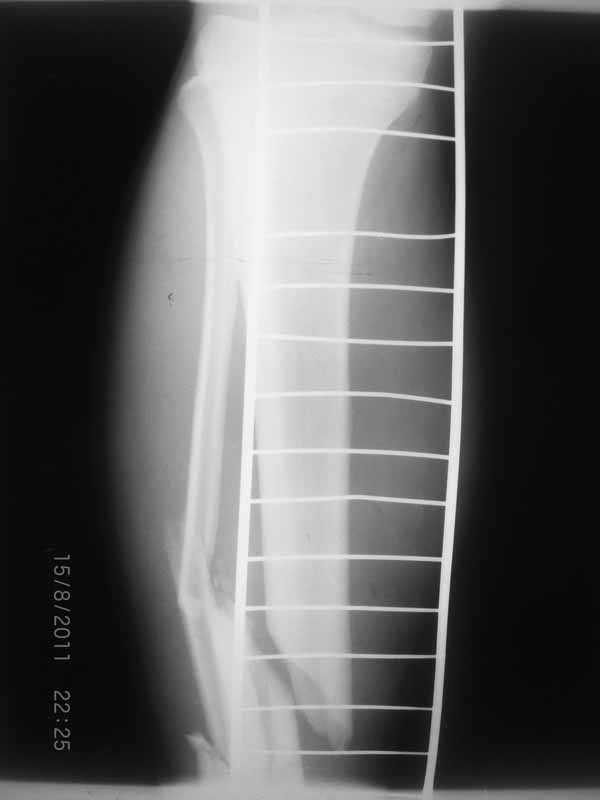

Примерная ситуация. Пациент 37 лет. Синтезировали где-то пластинкой. Попал к нам через 2 месяца.

19 апреля убрали через проколы пластину с винтами, пересекли fibula, наложили аппарат.

Немного потянули по оси, убрали вальгус, ротацию. 22 апреля (на 3-е сутки) заштифтовали окончательно. 29 апреля выписали из отделения. На все ушло 10 дней.

С уважением, Никита Заднепровский